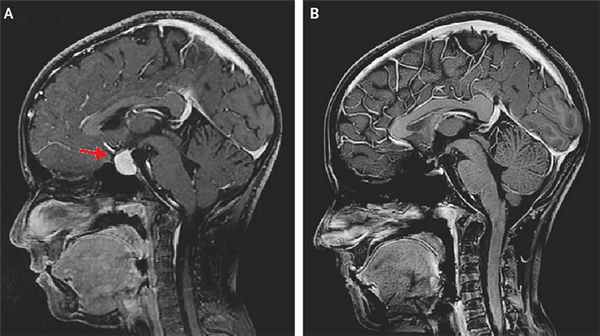

Диагностика аденомы гипофиза: тщательные гормональное и офтальмологическое обследования и нейровизуализация. Магнитно-резонансная томография — основной метод диагностики, позволяет выявить аденомы размерами менее 5 мм, однако, даже с учётом этого, примерно у 25–45% пациентов визуализировать аденому не удаётся. Компьютерную томографию применяют только в экстренных ситуациях при невозможности провести магнитно-резонансной томографии для исключения тяжёлых осложнений.

- Магнитно-резонансная томография — основной метод диагностики, позволяет выявить аденомы размерами менее 5 мм, однако, даже с учётом этого, примерно у 25—45% пациентов визуализировать аденому не удаётся.